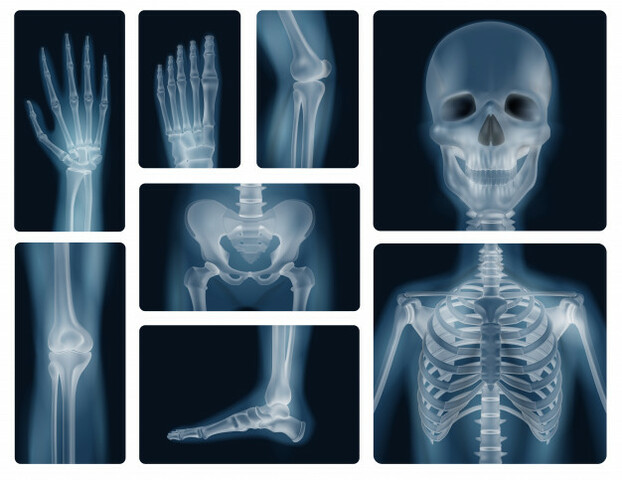

Disparos rayos x realistas huesos humanos 1284 29690

Historia de los Rayos X